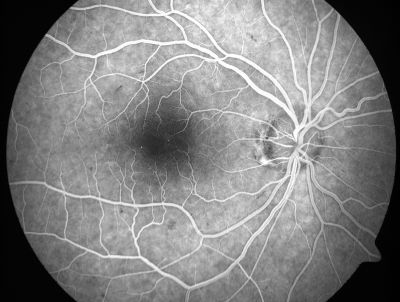

Retinal Vasculopathy associated with Facioscapulohumeral Muscular Dystrophy early fa

59-year-old woman had a blood pressure spike to 170/90 and was on medications for that. She does have facioscapulohumeral muscular dystrophy, which runs in her family. She has a cousin with the same disorder.

VISUAL ACUITY: Her vision is 20/25 OU. IOP: OD 21, OS 18.

There is no posterior vitreous separation, telangiectatic vessels near the macula. There are patchy retinal hemorrhages. There is no edema or proliferation.

Keywords: diabetic like; systemic disease; vasculopathy; hemorrhage; bdr